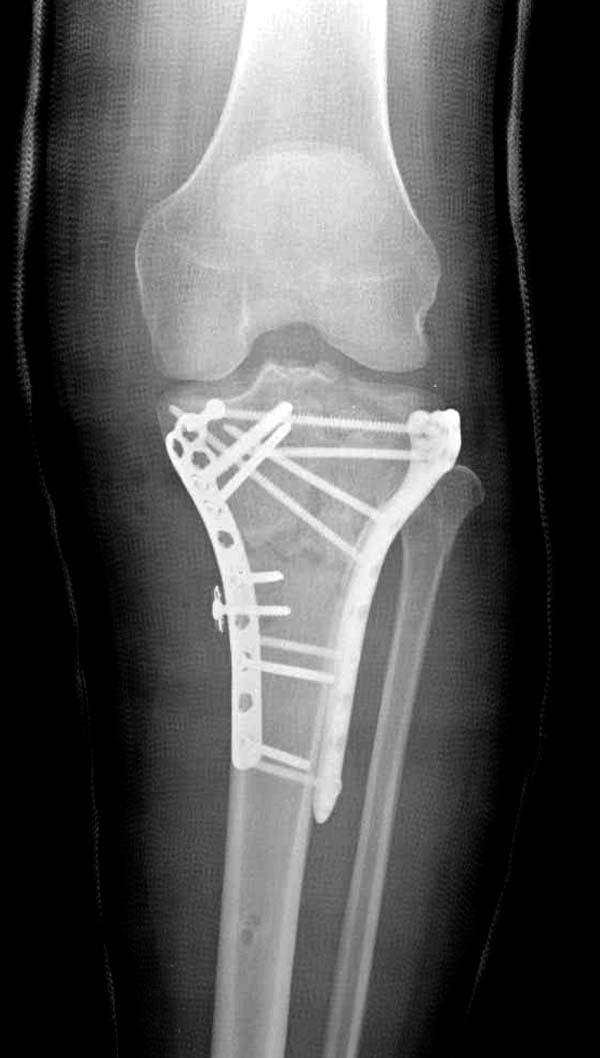

На боковом рентгене, явный задний смещенный компонент. КТ поможет увидеть "вершину" перелома, куда надо поставить антискользящую пластину из заднего или задне-медиальнего доступа. Для стабилизации боковой колонны традиционный боковой доступ через Girdle tubercle с длинной блокирующей пластиной. Одна задняя подпорка не удержит медиальную колонну, требуется длинная медиальная пластина.

Пластин для медиальной колонны не бывает, и поэтому подойдет любая тонкая пластина. Сегодня отходим от установки для тибиал плато толстых пластин, больше, чем 3.5 мм. Задача удержать, а нагрузка разрешается только после сращения в 3 мес., и поэтому нет смысла устанавливать толстые пластины

Перелом сложный, и для окончательного успеха потребуется арсенал фиксаторов и наличие опыта разных доступов. К успеху приведет только тщательное планирование. Возможно, фиксировать не удастся все за раз. Если во время операции возникнет опасность развития отека в ране, “damage control” операцию надо отложить, лучше поэтапно, чем осложнение.